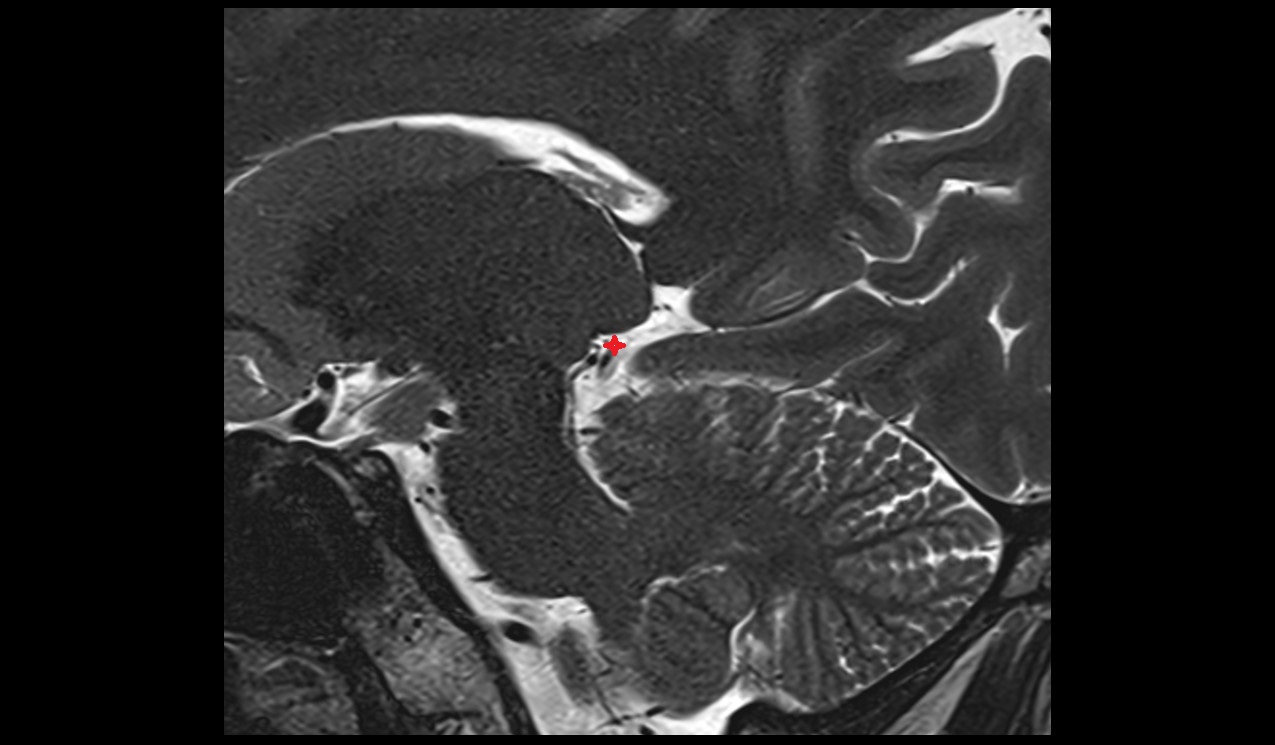

- Temporomandibular joint

- Mandibular condyle

- Mandibular fossa

- Articular disc of temporomandibular joint

- Articular eminence